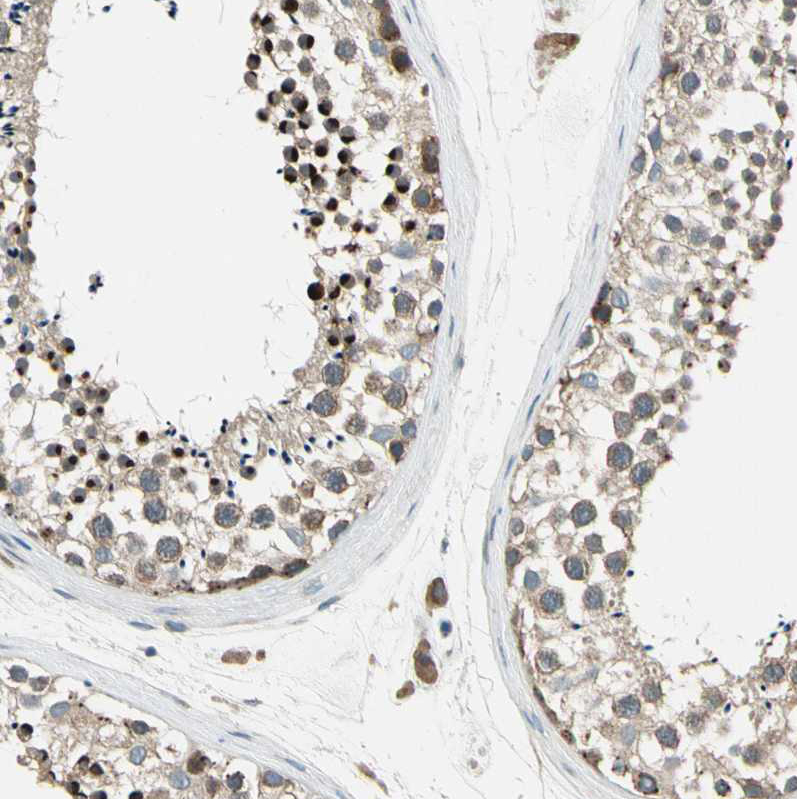

Immunohistochemical staining of human testis shows moderate cytoplasmic positivity in cells in seminiferous ducts.